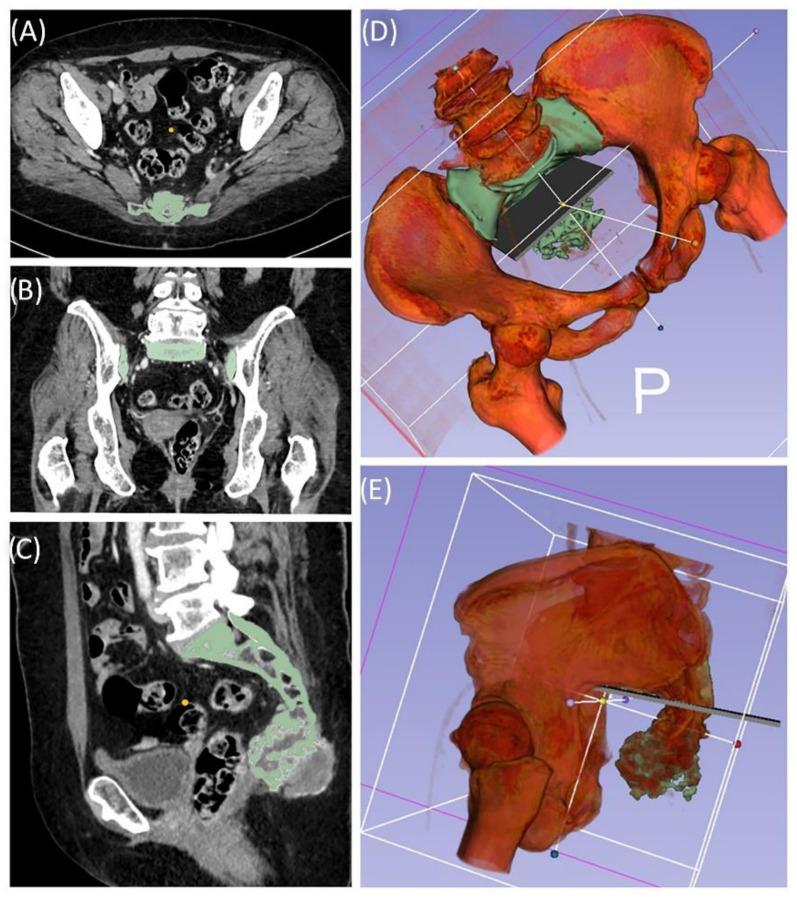

The combination of 3D printing and navigation promises improvements in surgical procedures and outcomes for complex bone tumor resection of the trunk, but its features have rarely been described in the literature. Five patients with trunk tumors were surgically treated in our institution using a combination of 3D printing and navigation. The main process includes segmentation, virtual modeling and build preparation, as well as quality assessment. Tumor resection was performed with navigated instruments. Preoperative planning supported clear margin multiplanar resections with intraoperatively adaptable real-time visualization of navigated instruments. The follow-up ranged from 2-15 months with a good functional result. The present results and the review of the current literature reflect the trend and the diverse applications of 3D printing in the medical field. 3D printing at hospital sites is often not standardized, but regulatory aspects may serve as disincentives. However, 3D printing has an increasing impact on precision medicine, and we are convinced that our process represents a valuable contribution in the context of patient-centered individual care.

摘要